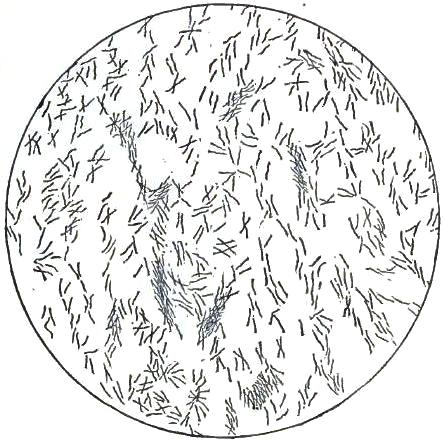

| FIGURE | |

| 1. | MICROCOCCI |

| 2. | BACTERIA |

| 3. | BACILLUS MALARIÆ |

| 4. | BACTERIA FROM GELATIN SOLUTION |

| 5. | VIBRIOS IN GELATIN CULTURE-FLUID |

| 6. | PROTOCOCCUS FROM SLIDES EXPOSED OVER SWAMP-MUD |

| 7. | BACILLI FROM SWAMP-MUD |

| 8. | BACILLI FROM SEPTICÆMIC RABBIT |

| 9. | BACILLI FROM HUMAN SALIVA |

| 10. | BACILLUS ANTHRACIS |

| 11. | BACILLUS TUBERCULOSIS |